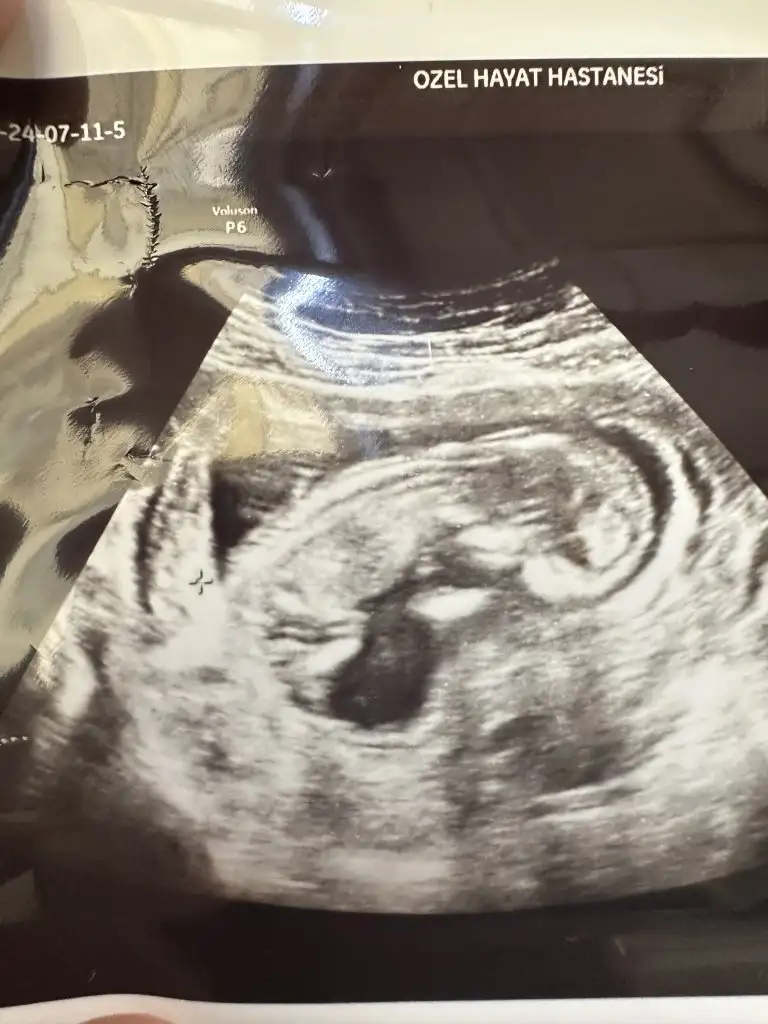

Az önce çekildik. 12+0 ız. Cinsiyet tahminleri nedir arkadaşlar?

• IMG_20240711_222412.webp

IMG_20240711_222412.webp